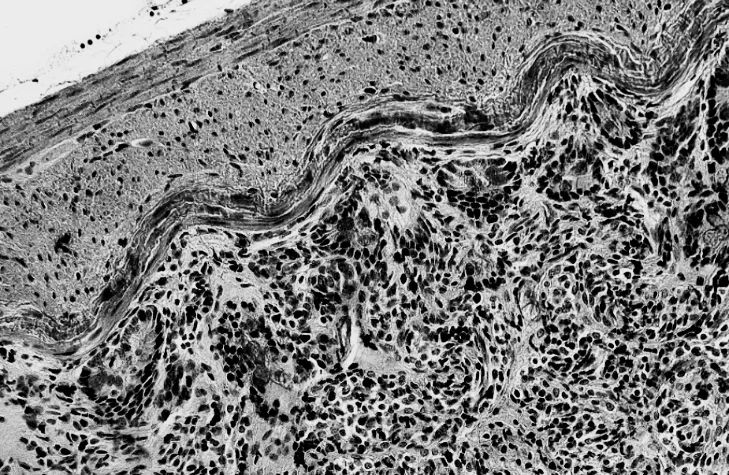

Rat Intestine Tissue,40x,EVOS FL Auto 2拍摄